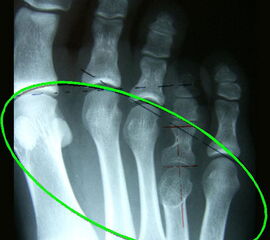

Die Kallusdistraktion hat sich neben der Verlängerungsosteotomie und Knochenspaninterposition zu einem etablierten Verfahren zur Verlängerung von Metatarsalia/Metacarpalia bei longitudinalen Reduktionsdefekten, die posttraumatisch oder postoperativ entstehen können, meist jedoch zu den angeborenen Fußfehlbildungen zählen, durchgesetzt 12345678

(Giebel 1993, Klauser 2009). Eine Korrektur dieser Deformität ist – insbesondere, wenn es sich um angeborene Fußfehlbildungen wie die der Brachymetatarsie handelt – aus rein funktionellen Gründen (aufgehobener Metatarsalebogen, gestörtes Alignment) und der zu erwartenden Sekundärveränderungen erforderlich 910 (Klauser 2009). Am Fuß stellt jedoch die Verlängerung kleiner Röhrenknochen - unter Verwendung eines externen Fixateursystems - ein für den Patienten und behandelnden Chirurgen / Orthopäden sehr mühsames, unkomfortables und mit vielen Komplikationen behaftetes Verfahren dar 111213145 (Klauser 2009, Ruffer 2006). Im Folgenden wird daher ein innovatives Operationsverfahren unter Nutzung eines internen, winkelstabilen Titan-Minifixateurs dargestellt, welches dem Verfahren mit externem Fixateur hinsichtlich der Nachbehandlung, aber vor allem auch der Komplikationsrate deutlich überlegen ist (Klauser 2009).

• Röntgenaufnahmen beider Füße a.p. und streng seitlich unter Belastung sowie Schrägaufnahme beider Füße ohne Belastung.

• Ausmessen der zu verlängernden Strecke des betroffenen Metatarsale und damit Beurteilung der Defektstrecke zur Rekonstruktion des Metatarsaleindex.